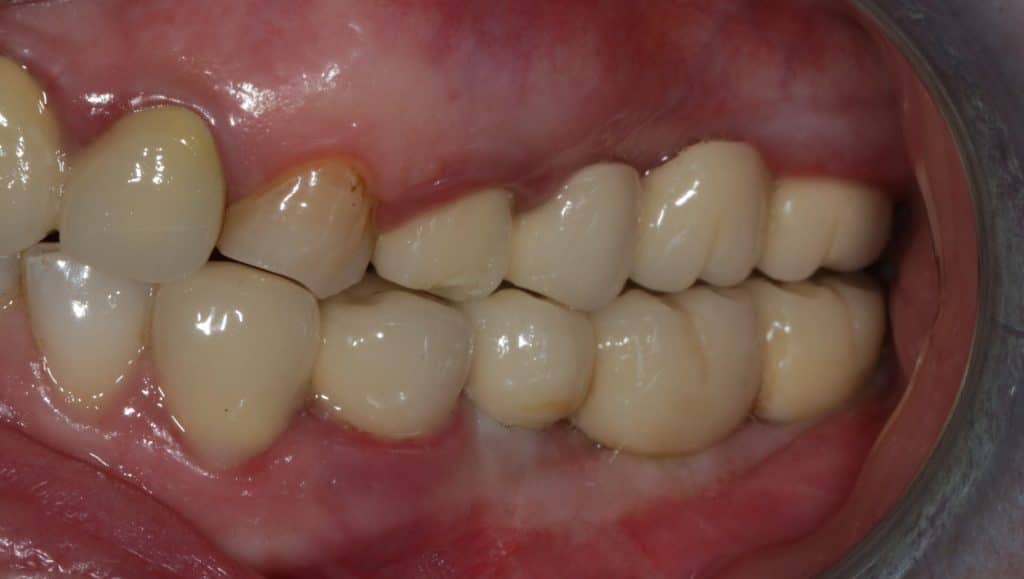

Clinical situation after second surgery- Lateral view

Final prosthetic rehabilitation- lateral view